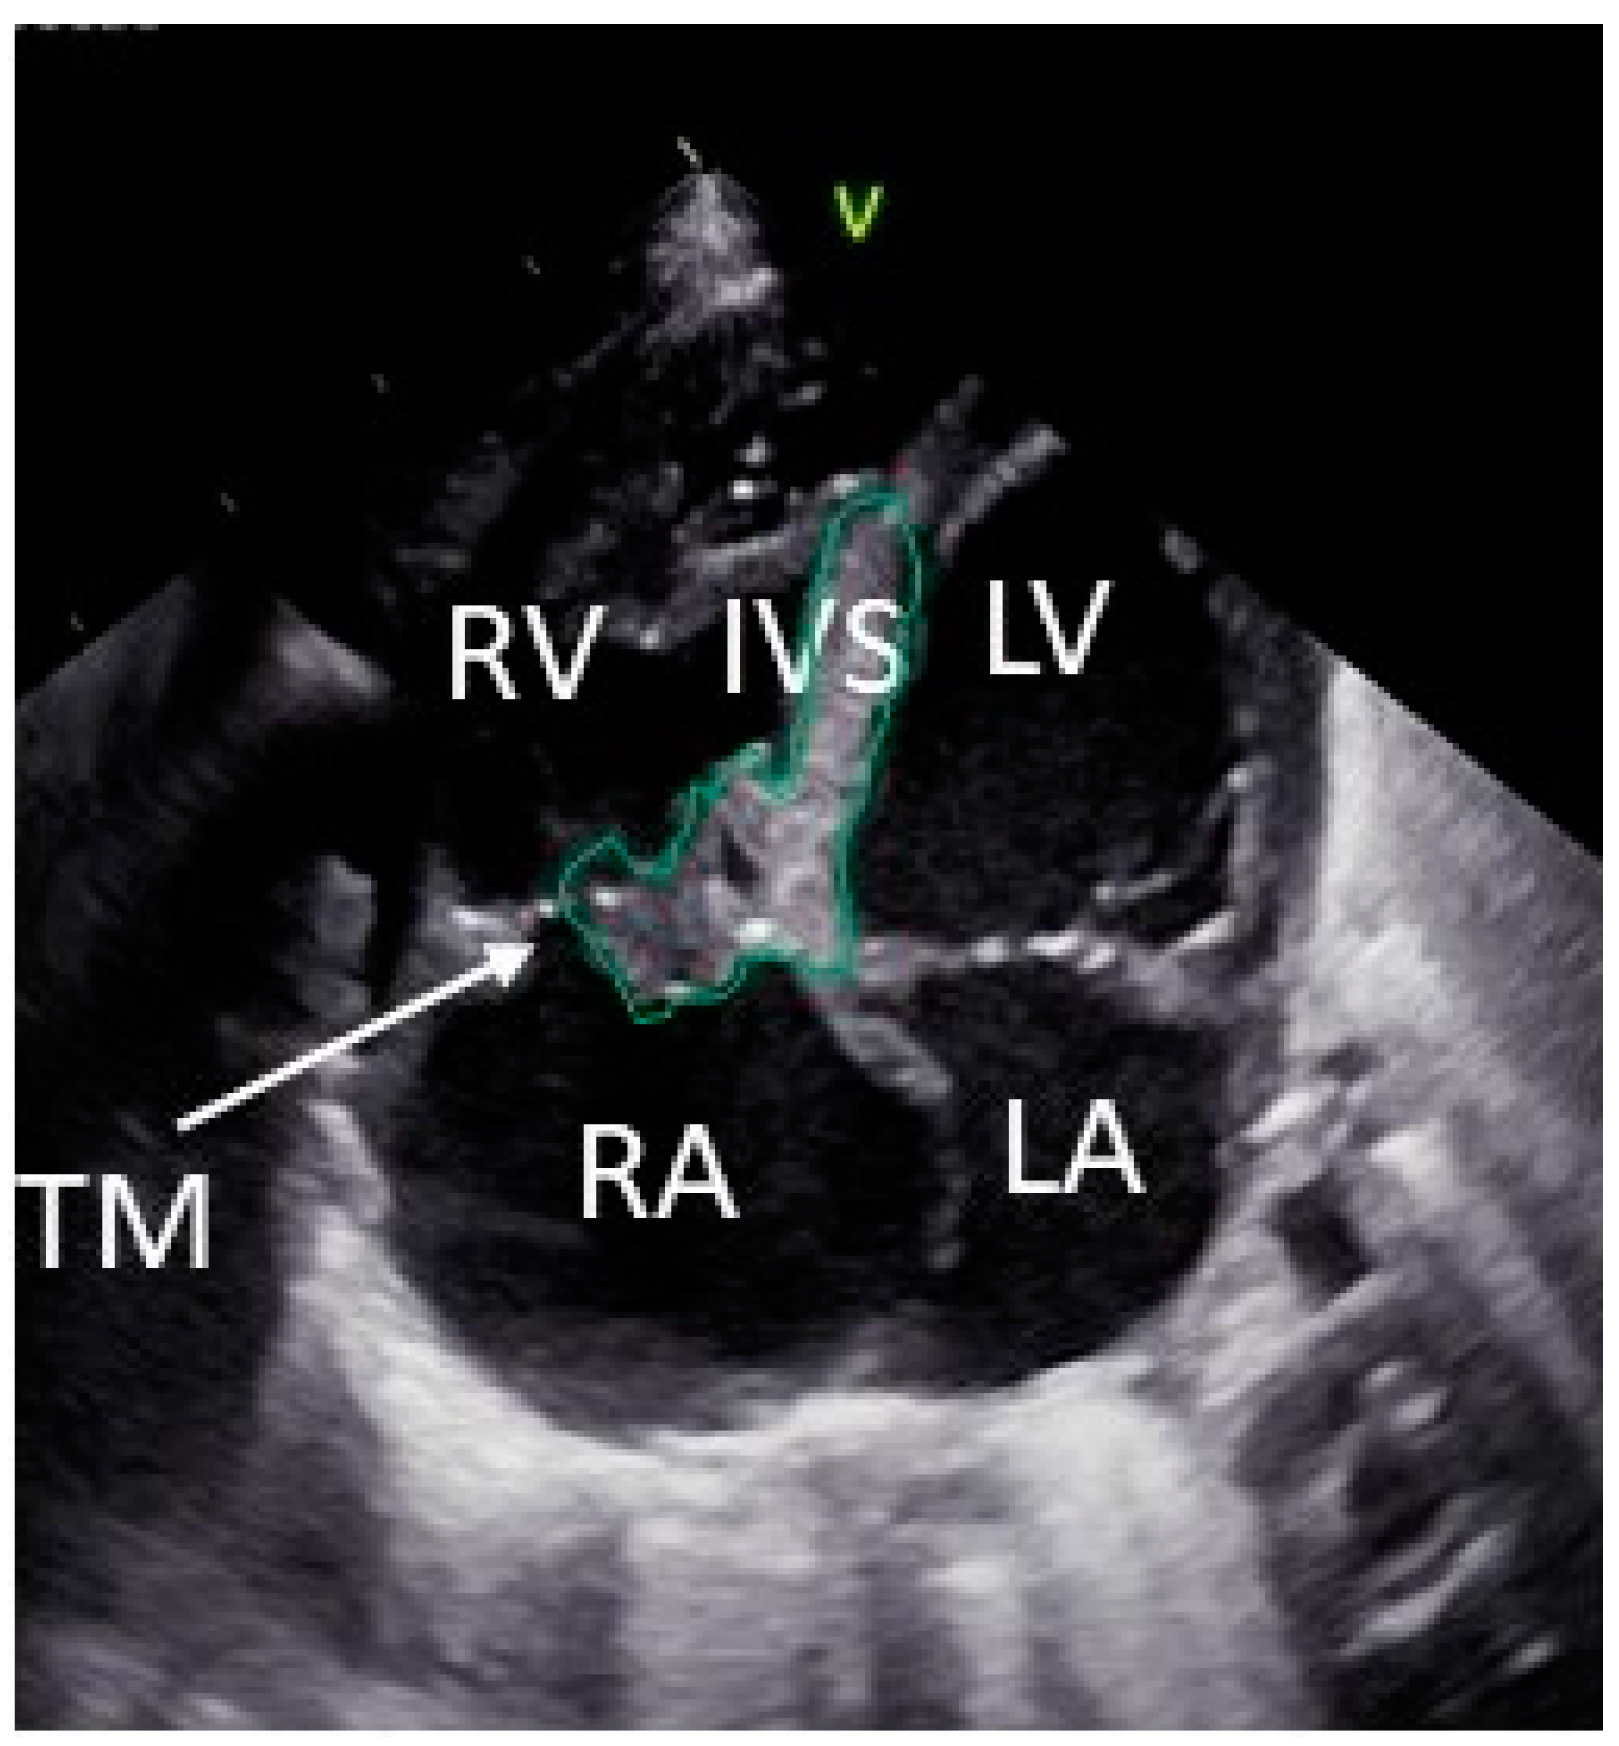

2. Case Description